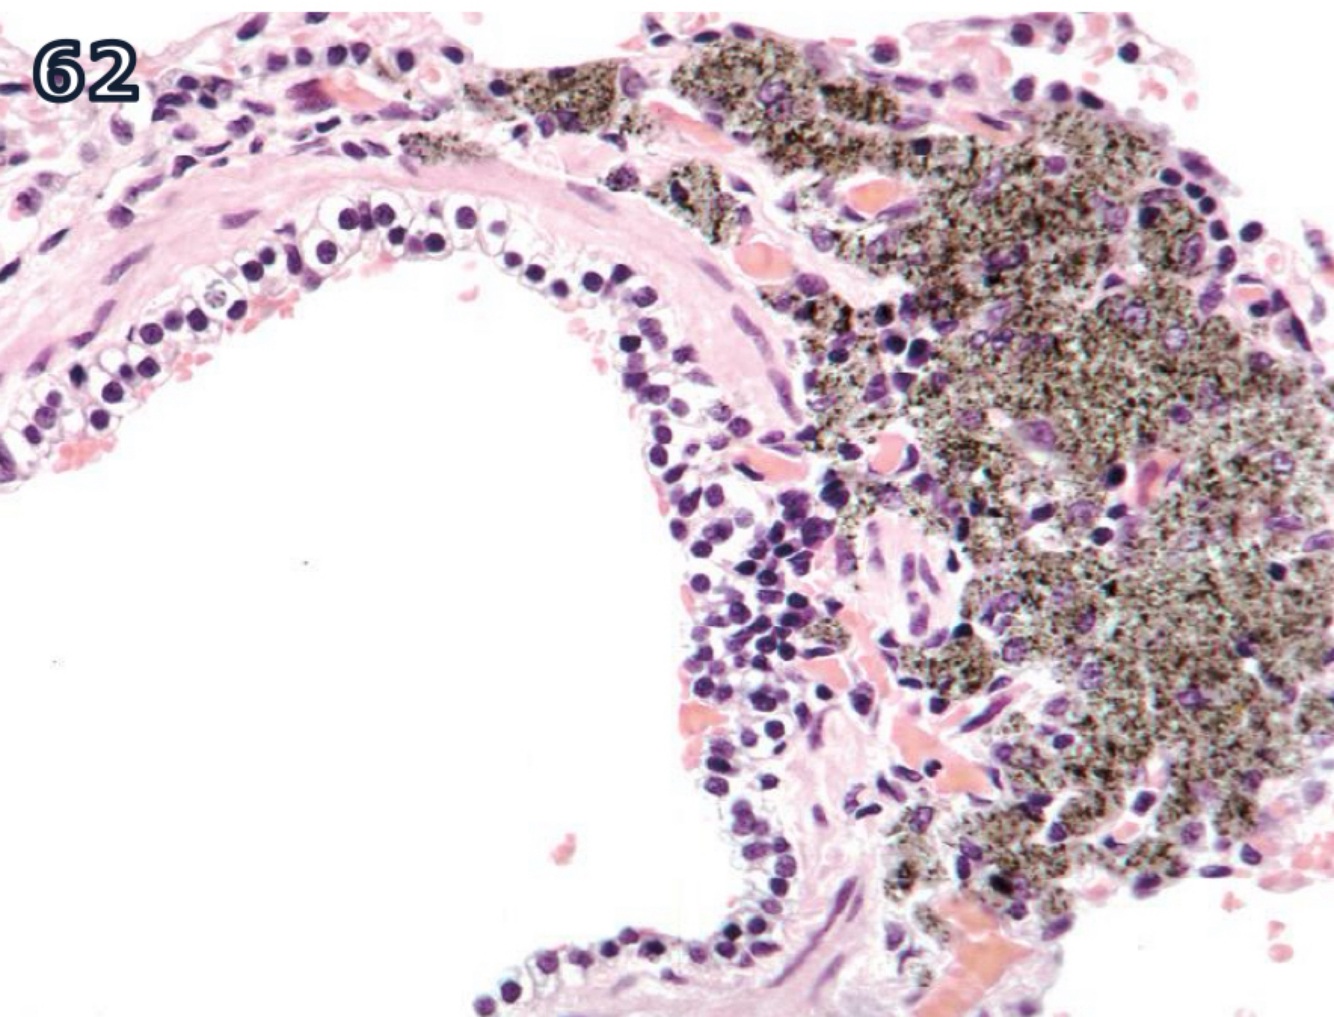

prasites infecting or consuming RBCs liberate heme during proteolysis of Hgb

free heme is toxic but parasites have evolved to aggregate it into heme dimers

accounts for blacking of migration tracts by juvenile liver flukes in ruminants + for black speckling of lungs in macaques infested w/ lung mite